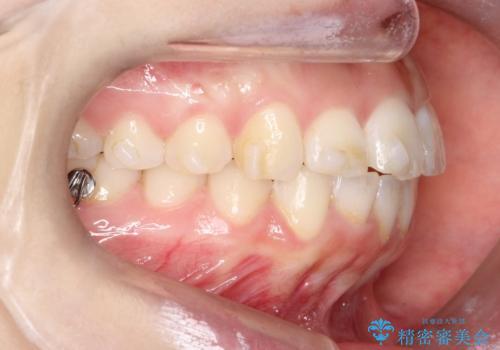

【インビザライン】前歯が出ているのを治したい

- 前歯が出ていることを主訴に来院されました。

前歯の突出感が改善され、満足していただきました。